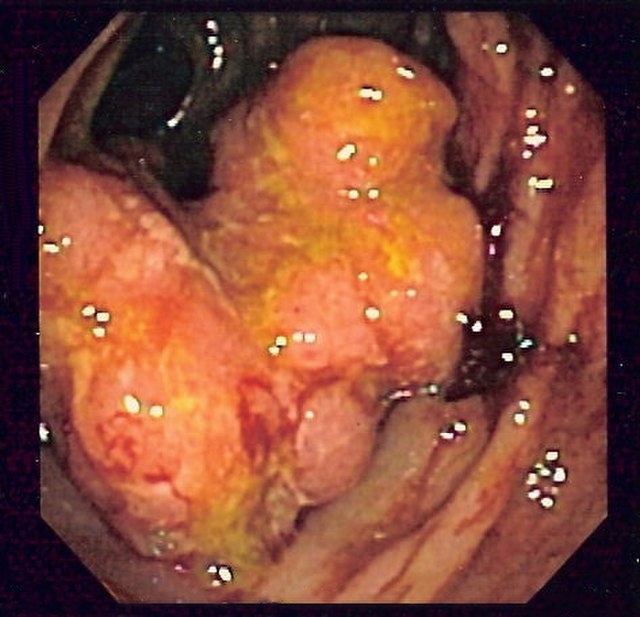

Sometimes the tumours grow deep inside the body. If there is plenty of room for them to grow before they cause symptoms, they can easily become very big and have formed many metastases before the person affected becomes aware of the problem. Lung cancers, stomach cancers and bowel cancers are rather like this.